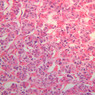

The adenohypophysis arises from oral ectoderm and forms the largest subdivision of the pituitary gland. It consists of three regions: (1) pars tuberalis, which wraps around the pituitary stalk; (2) pars distalis, which makes up most of the anterior portion of the adenohypophysis; (3) pars intermedia, which lies between the pars distalis and the pars nervosa of the neurohypophysis and is characterized by the presence of colloid-filled cysts. In H&E-stained sections, the adenohypophysis is darker than the neurohypophysis (B-63, H&E [2.5x, 10x-labeled, 20x]; B-64, aldehyde fuchsin [2.5x, 10x, 20x, 40x]; B-65, trichrome [2.5x]).

The neurohypophysis arises as an outpocketing of neuroectoderm from the floor of a portion of the brain called diencephalon. It is divisible into the pars nervosa, which forms the posterior portion of the main mass of the pituitary, and the infundibulum, or pituitary stalk. In H&E-stained sections, the neurohypophysis is distinctly eosinophilic. The adenohypophysis (anterior pituitary) has three different types of secretory cells, which are best visualized in the trichrome-stained preparation on slide B-65: (1) acidophils have a reddish staining cytoplasm, owing to the presence of secretory granules. These cells secrete growth hormone (GH) and prolactin (PRL); (2) basophils are slightly larger cells with bluish staining granules present in the cytoplasm. These cells tend to occur in small groups or clusters. Basophils are responsible for the production of thyroid stimulating hormone (TSH), adrenocorticotrophic hormone (ACTH), and the gonadotrophic hormones follicle stimulating hormone (FSH) and luteinizing hormone (LH ); (3) chromophobes or C cells are smaller cells and have only a small amount of poorly staining cytoplasm (B-63, H&E [2.5x-labeled, 10x, 20x, 40x-labeled] [2.5x, 10x, 20x, 40x-labeled]; B-65, trichrome [2.5x, 10x, 20x, 40x-labeled] [2.5x, 10x, 20x, 40x] [10x, 20x, 40x-labeled] [2.5x, 10x, 20x, 40x] [2.5x, 10x, 20x, 40x]). What is the target organ of each of the hormones produced by the adenohypophysis? Note the rich vascularity of the adenohypophysis. Can you describe the blood supply and its significance?